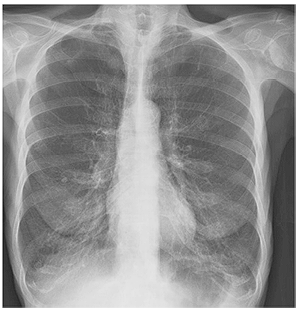

Uma paciente com 64 anos de idade é atendida em ambulatório de geriatria, onde relata tosse crônica há 10 anos. Há 3 dias, ela apresenta escarro de cor amarelo-esverdeado, principalmente no período noturno, com notável dispneia. Refere fumar desde os 24 anos de idade, em uma média de 10 cigarros por dia, além de ser portadora de tireoidite de Hashimoto, hipertensão e diabetes.

No exame clínico, a paciente apresenta-se lúcida e orientada, com 16 incursões respiratórias por minuto, afebril, pressão arterial de 130 mmHg × 80 mmHg, roncos na base pulmonar bilateral, hidratada e com diurese preservada.

São medicações de uso constante da paciente: levotiroxina, enalapril, sinvastatina, anlodipino, sitagliptina e pioglitazona.

Os resultados de exames complementares feitos no dia da consulta revelam: creatinina de 0,7, ureia de 30, leucócito de 5.000, sem distúrbios hidroeletrolíticos, com PCR de 40. A imagem da radiografia de tórax é mostrada a seguir.